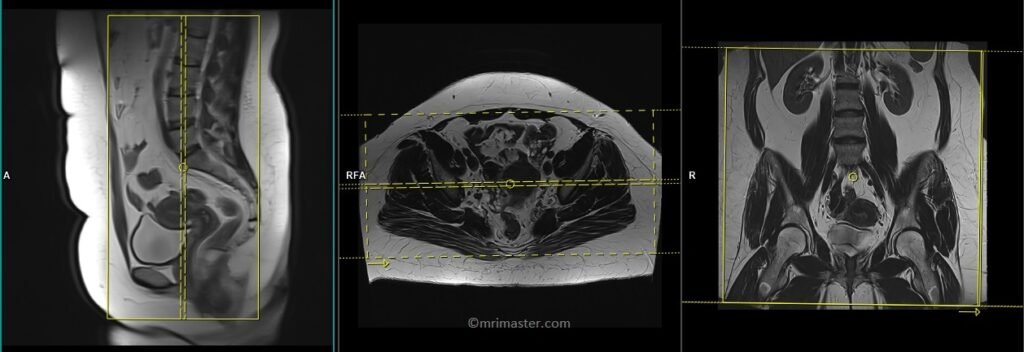

T2 stir coronal 5 mm LARGE FOV

Plan the large field of view (FOV) coronal slices on the sagittal plane and position the block parallel to the lumbar spine. The positioning block should also be checked in the other two planes. An appropriate angle needs to be established in the axial plane, which runs parallel to the right and left hip joint. The slices must be sufficient to cover the entire abdomen and pelvis, ranging from the anterior abdominal wall to the sacrum. The FOV must be large enough to cover the abdomen and pelvis (typically 380mm-400mm). Large FOV scans are usually performed to evaluate the local spread of the pathology and assess the para-aortic and pre-sacral nodes.

Parameters

TR 4000-6000 | TE 110 | FLIP 160 | NEX 2 | SLICE 5MM | MATRIX 384X320 | FOV 380-400 | PHASE R>L | GAP 10% | TI 150 |